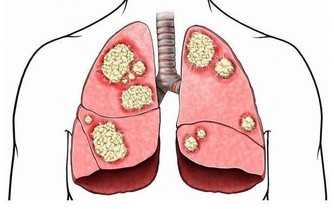

我們要知道,當身體出現腎虛或腎虧的時候,這兩者之間最大的一個區別就是嚴重程度不同。因為腎虛是腎臟虛弱導致身體出現不適的情況,如果腎虛較為嚴重,在一定的情況下,才會發展為腎虧,所以說,腎虧相對比腎虛來說,程度上較為嚴重。

腎虛是由於腎不能固精,導致腎精嚴重流失,體內的腎精就會匱乏。如果自身患有腎虛,我們就會出現臉色蒼白、喘息以及頭髮還會出現嚴重脫落等症狀表現,如果腎虛更嚴重的話,甚至還會導致男性不育等情況。腎虧的症狀主要表現為腰膝酸軟、乏力、心煩易怒以及眩暈耳鳴等。

因此,如果發現我們的腎臟出現問題,就要定期去醫院檢查,做相關的治療,聽從醫生的指導把我們的腎臟調理好,治療期間不能半途而廢,否則會導致後期病情加重發展為腎虧,加重腎臟負擔,影響自身的健康。